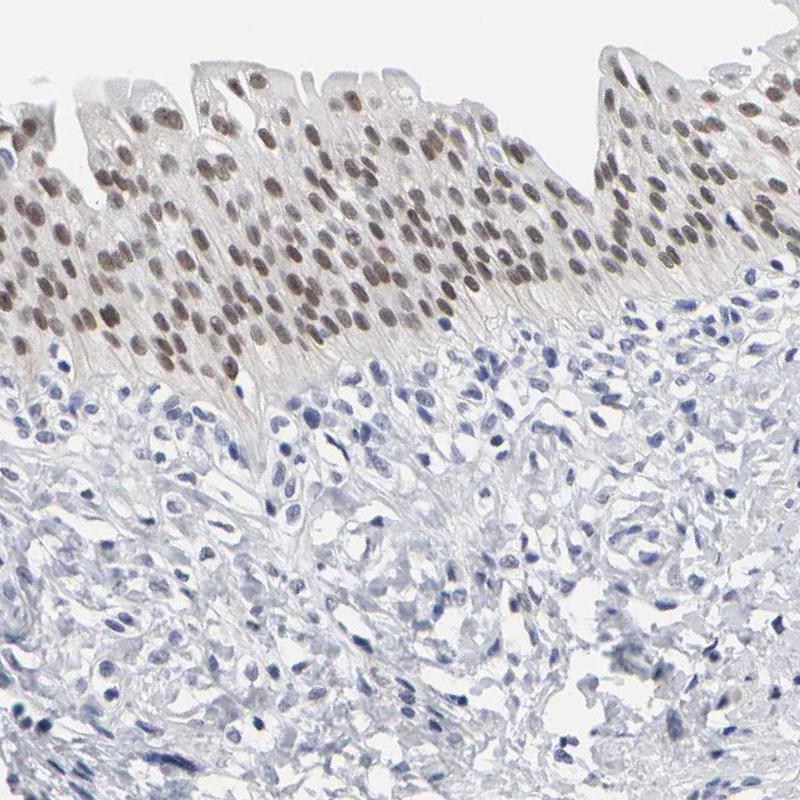

Immunohistochemical staining of human prostate shows strong nuclear positivity in glandular cells.